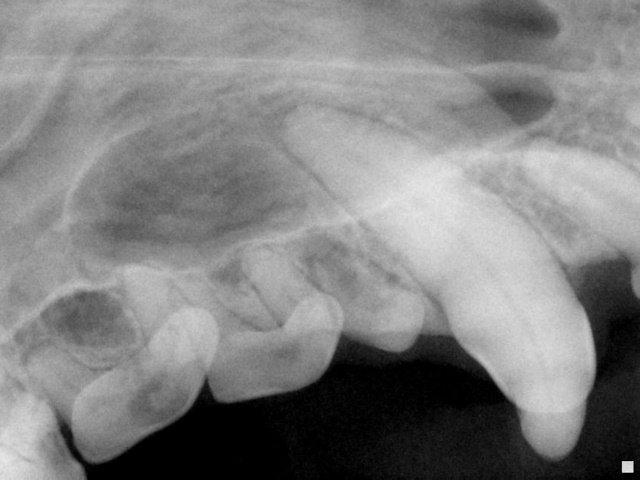

Dental radiograph of this canine tooth does not reveal any root or root tip abnormalities.